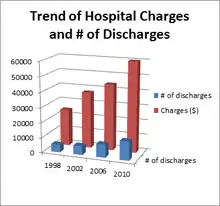

Statistics from the AHRQ show that there were 12,532 hospital discharges from C2 fractures in the US during 2010. The mean healthcare costs were $17,015 and the "national bill" or the aggregate charges were $749,553,403. Only 460 in-hospital deaths related to the C2 fracture occurred. From 2000 to 2010, the number of discharges has increased from 4,875 to 12,532, almost a 250 percent increase. Mean health care costs went from $24,771 to $59,939.[4]